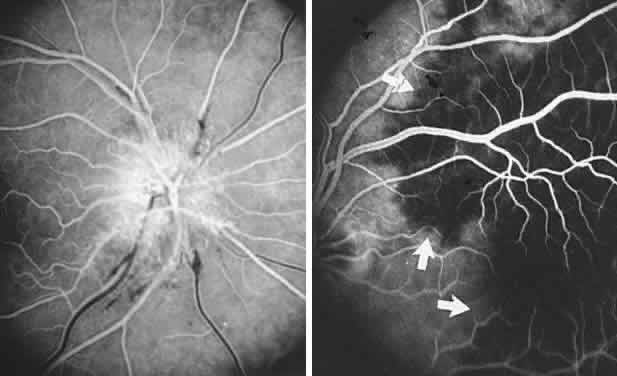

angiographic studies. Arch Ophthalmol 102:981, 1984 90. Newman NJ: Leber's hereditery optic neuropathy: new genetic considerations. Arch Neurol 50:540, 1993 91. Newman NJ, Lott MT, Wallace DC: The clinical characteristics of pedigrees of Lebers' hereditary optic neuropathy

causing intracranial hypertension without ventriculomegaly. Arch Neurol 48:740, 1991 180. Katz B: The dyschromatopsia of optic neuritis. Trans Am Ophthalmol Soc 93:685, 1995 181. Mojon DS, Rösler KM, Oetliker H: A bedside test to determine motion stereopsis using the Pulfrich phenomenon. Ophthalmol 105:1337, 1998 182. Selhorst JB, Saul RF: Uhthoff and his symptom. J Neuroophthalmol 15:63, 1995 183. Keltner JL, Johnson CA, Spurr JO et al: Visual field profile of optic neuritis: one-year follow-up in the optic